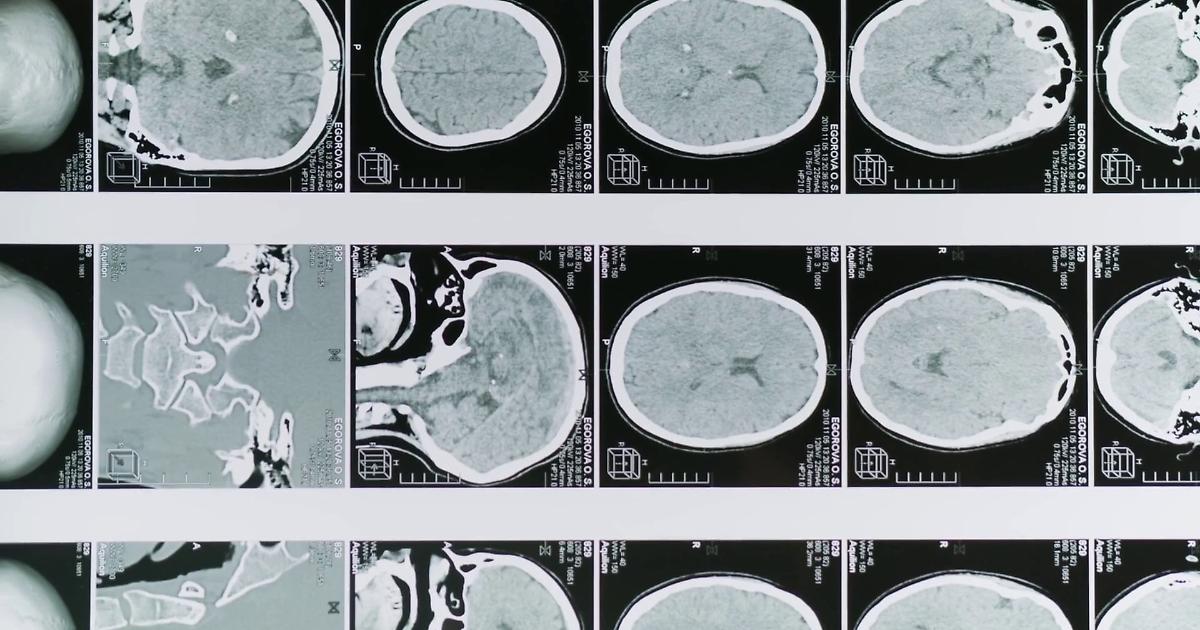

Glioblastoma, le molecole naturali migliorano la chemioterapia